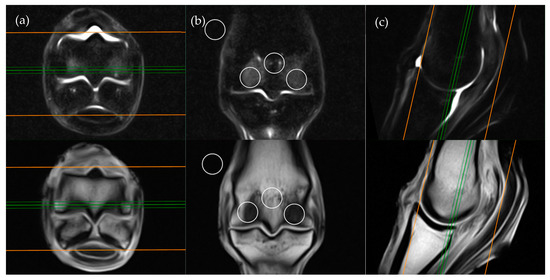

Images were viewed by a veterinary radiologist experienced with the interpretation of low-field equine fetlock MRI examinations (AY). MRI studies were viewed in “digital imaging and communications in medicine” (DICOM) format on an interactive DICOM viewer workstation (Osirix MD). Standardised regions of interest (ROIs) of 2 cm2 were imported into each study. The ROIs were positioned in predetermined locations for each plane of the STIR sequences (Figure 1, Figure 2, Figure 3 and Figure 4) then copied across to the corresponding T1W slice. For every intraosseous ROI measured, a background ROI was also placed external to the anatomy in the same image at a consistent, predetermined location. One to three signal to noise ratios (SNRs) were calculated for each image examined in order to evaluate signal changes between images rather than absolute signal value. SNR is the ratio between the amplitude of the MR signal of a tissue and the standard deviation of the amplitude of the background noise. Use of SNR also allowed for image window and level settings to be adjusted subjectively for each study in order to maximize visualization of intraosseous STIR hyperintensity. Each limb was graded poor, satisfactory, good or excellent for quality of fat suppression in the STIR sequences. The experimental protocol was divided into two parts; blinded and unblinded.

The transverse image located two slices distal to the level of the physeal vasculature was chosen for the transverse plane measurements (Figure 2). Three ROIs were placed; centrally within the distal palmar/plantar margin of the lateral and medial condyles and immediately between these ROIs at the palmar/plantar aspect of the sagittal ridge. The background ROI was placed at the lateral or medial surface of the limb, at the palmar/plantar half of the condyles and in alignment with the three intraosseous ROIs.

Figure 2. STIR FSE (top row) and T1W GRE (bottom row) MRI images in (a) transverse; (b) frontal and (c) sagittal planes; demonstrating the location of ROI placements in a transverse plane. The green lines on the frontal and sagittal images show the standardized orientation and location of the transverse slice for ROI placement. The orange lines show the extent and orientation of all the transverse slices acquired in the MRI study.